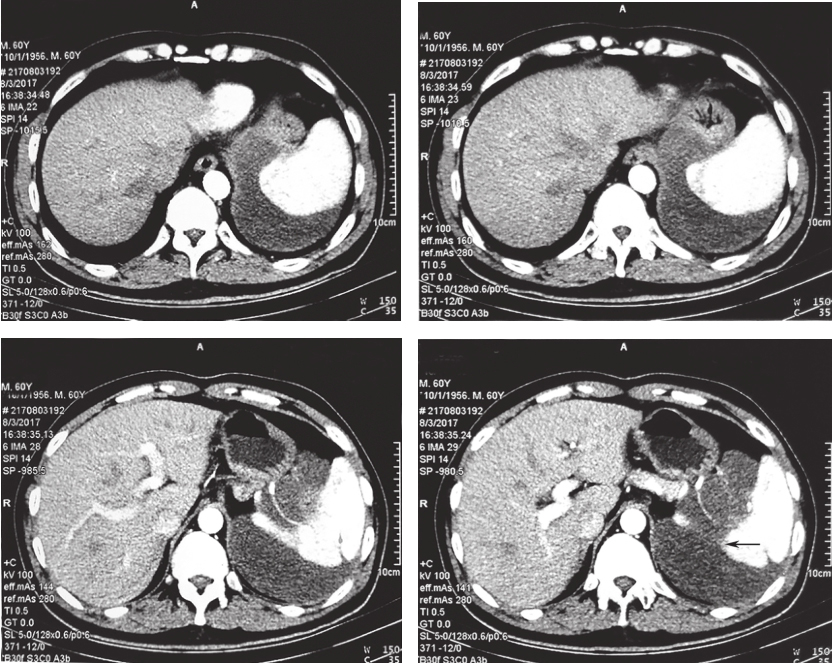

患者服药12个月后复查CT示:与前片比较,软组织密度影范围未见明显缩小,最大截面积约12.9cm×10.3cm,评估为稳定状态,伊马替尼术前治疗疗效已到最大反应效应;患者存在继发耐药风险。建议患者可终止术前治疗,择期行手术切除病灶,但患者拒绝(图1)。

图1 2017年11月30日增强CT